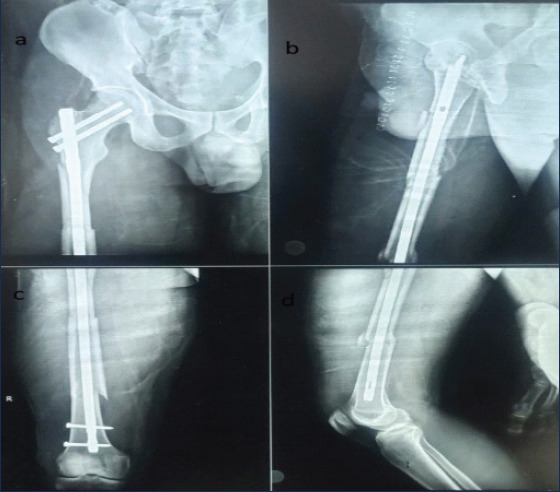

Case report: A 35-year-old man with multiple-level femoral fractures at the subtrochanteric, diaphyseal, and supracondylar femoral regions - a condition known as double-SFFs - presented to our emergency department due motor vehicle collision. Intramedullary nailing was done without the use of a fracture table for fixation, and because there was a completely separated femoral fragment between the fracture lines, fracture reduction was difficult during reaming due rotation of the middle fragment.

Conclusion: Double-segmental femur fractures are regarded as exceedingly uncommon injuries. Our results highlight that intramedullary nailing without a fracture table can yield excellent functional outcomes, with patients expected to achieve full weight-bearing by four months and a full range of motion thereafter.